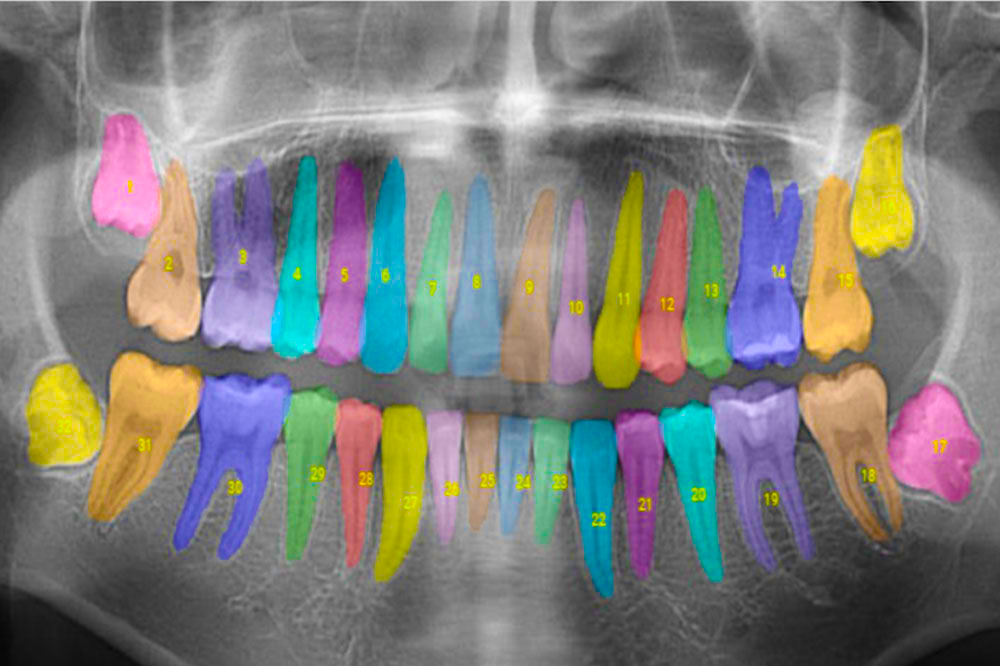

تصویربرداری رادیوگرافی یکی از پایه های اساسی تشخیص در دندانپزشکی است. با ورود یادگیری ماشین (Machine Learning) و بینایی کامپیوتری (Computer Vision)، تحلیل این تصاویر بسیار دقیق تر و سریع تر شده است. الگوریتم های یادگیری عمیق می توانند حتی تغییرات بسیار جزئی در تراکم استخوان یا ساختار دندان را شناسایی کنند که ممکن است توسط چشم انسان قابل تشخیص نباشد.

برای نمونه، سیستم های AI مانند Pearl Dental AI یا DentXray قادرند تصاویر رادیوگرافی را پردازش و نواحی مشکوک به پوسیدگی یا تحلیل استخوان را هایلایت کنند. این فناوری ها با استفاده از دیتاست های آموزشی وسیع، توانایی شناسایی انواع بیماری های پریودنتال، مشکلات ریشه و ناهنجاری های استخوانی را افزایش داده اند. علاوه بر تشخیص، این سیستم ها می توانند روند بیماری را در طول زمان دنبال کنند و با مقایسه تصاویر فعلی با تصاویر قبلی بیمار، میزان پیشرفت یا بهبود را گزارش دهند.

استفاده از این ابزارها در مطب های دندانپزشکی علاوه بر ارتقای کیفیت تشخیص، باعث افزایش اعتماد بیمار به دندانپزشک می شود، زیرا نتایج به شکل واضح و قابل مشاهده ارائه می گردد.